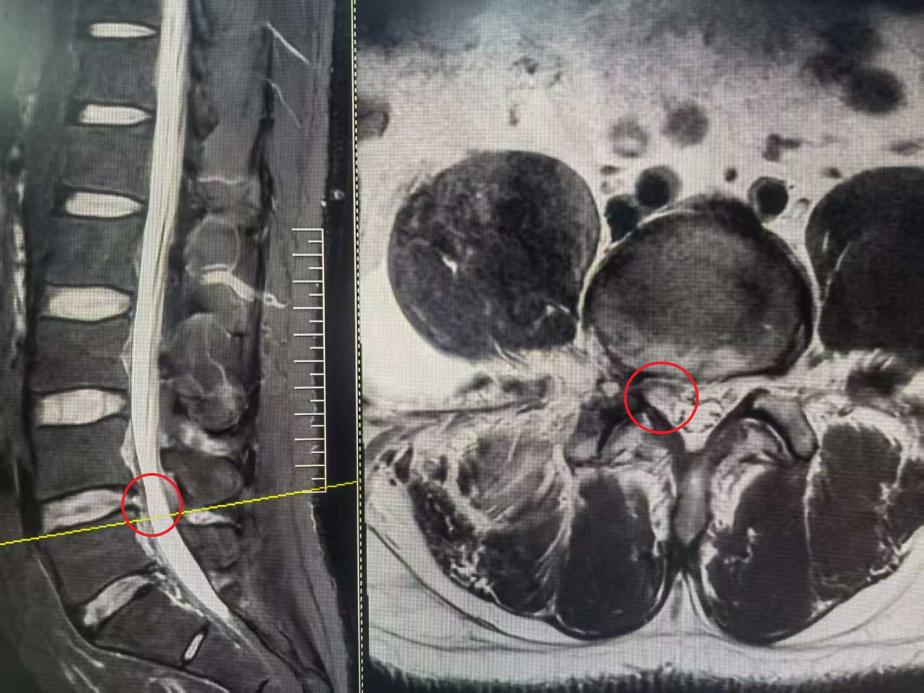

3个月前,王先生出现腰痛伴右下肢麻痛,活动受限,以下肢症状为主,经过保守治疗后症状不缓解,他慕名来到河南省直第三人民院脊柱微创外科,寻求微创治疗。

患者入院检查之后发现,病因是腰椎间盘脱出,压迫神经,导致右腿的疼痛麻木

入院检查腰椎磁共振

根据检查结果及患者症状和诉求,医生选择了椎间孔镜微创手术